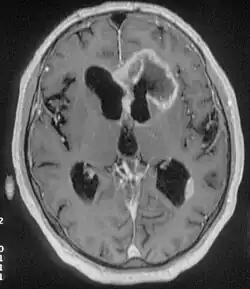

There are many different causes of frontal lobe epilepsy ranging from genetics to head trauma that result in lesions in the frontal lobes.[4] Although frontal lobe epilepsy is often misdiagnosed, tests such as prolonged EEG monitoring, video EEG and/or an MRI scan of the frontal lobes can be administered in order to reveal the presence of a tumor or vascular malformation.[4] Unlike most epileptic EEGs, the abnormalities in FLE EEGs precede the physical onset of the seizure and aid in localization of the seizure's origin.[4] Medications such as anti-epileptic drugs can typically control the onset of seizures, however, if medications are ineffective the patient may undergo surgery to have focal areas of the frontal lobe removed.[4]

Neuroimaging for diagnosis

Advancements in technology, has given rise to newer, more efficient methods of diagnosis, most prominent being in the domain of neuroimaging.[7] The high spatial resolution from fMRI has implications on certain brain regions contributing to memory.[7] The usage of task fMRI for examination of memory or other higher cognitive networks may also be used to predict ictal onset zone(s) in patients with FLE, giving the advantage of refinement of patient-specific analyses.[7] The use of multi-modal approaches in association with neuroimaging techniques like fMRI and MEG or EEG will be informative in characterizing atypical functional brain networks in FLE.[7] But, difficulty remains in the evaluation of potential compensatory mechanisms between patients with FLE with normal and impaired memory, without properly characterizing transfer of information during memory tasks.[7]

When both the amount and severity of seizures becomes uncontrollable and seizures remain resistant to the various anticonvulsants, a patient most likely will be considered for epilepsy surgery.[38] But, while performing it, there is the need for identifying or pinpointing the exact location of the seizure in the brain.[38] This, in recent times have been aided by some of the modern techniques such as, SISCOM i.e., subtraction ictal SPECT co registered to MRI, SPECT i.e. single-photon emission computerized tomography, brain mapping performed before the surgery and functional MRI (fMRI), especially for the language area mapping.[38]